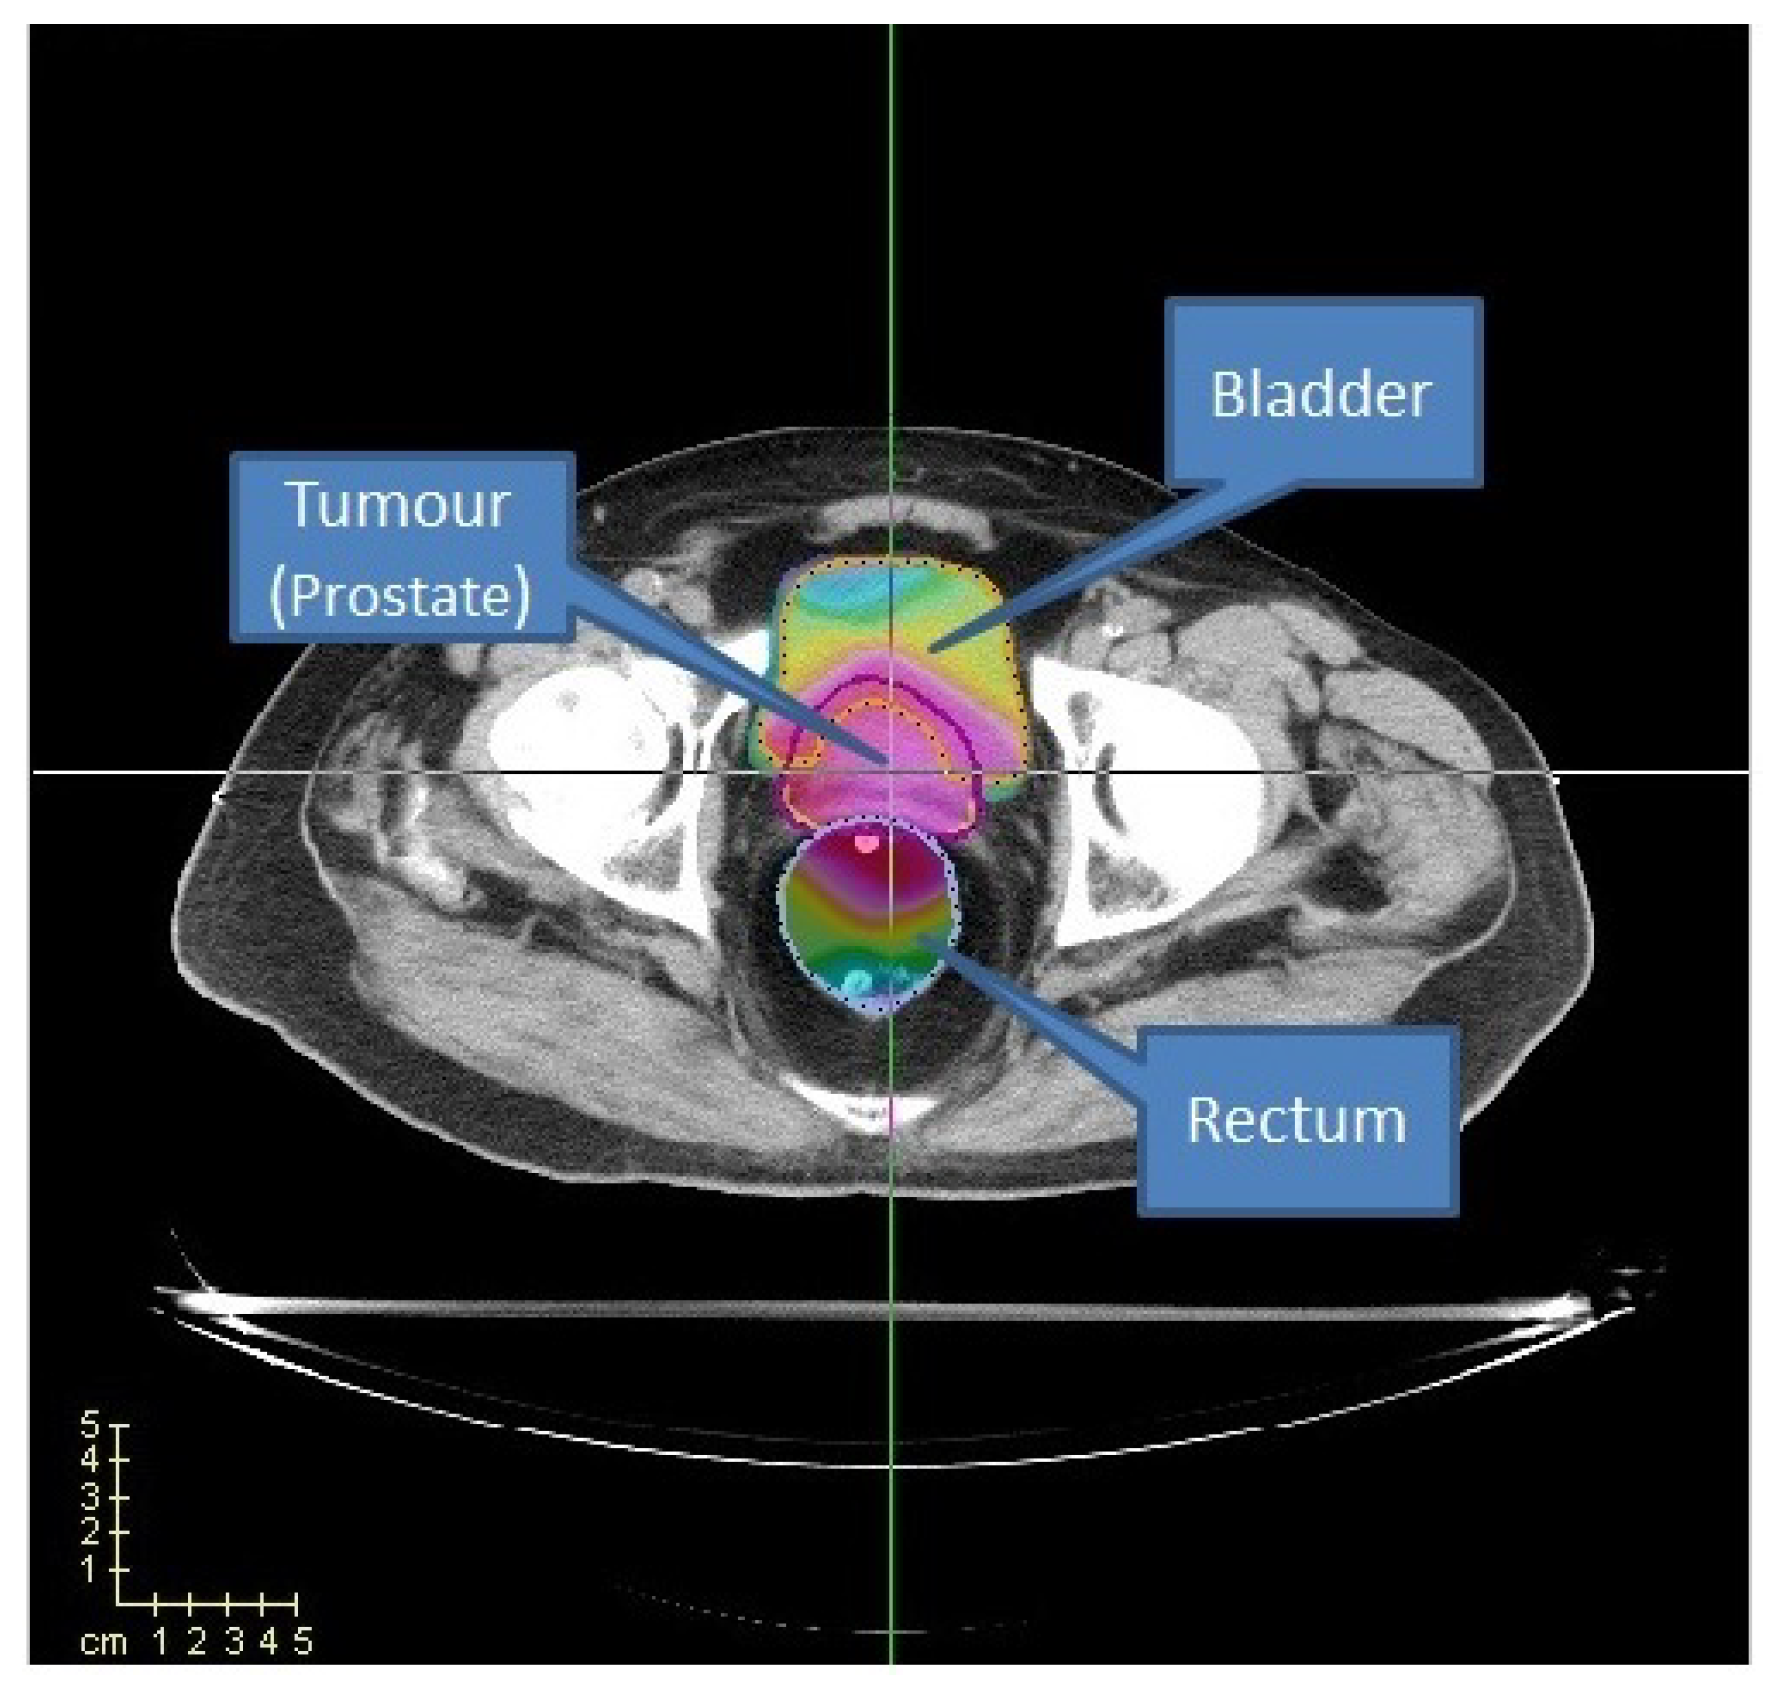

In this work, we perform a set of initial experiments on the prostate case instance from CERR package [37] and also examine a prostate case acquired from Clinica Alemana de Santiago, Chile. This particular patient is denoted as TRT001 [19]. We use this prostate case to evaluate the performance of the PSO algorithm introduced in Section 3.1. For the CERR and TRT001 cases, we consider three organs: the prostate, where the tumour is located, the bladder, and the rectum (see Figure 13). We label the rectum and the bladder as organs at risk (OARs) and the prostate as planning target volume (PTV).

Figure 13. Prostate case from CERR. Two OARs (bladder and rectum) are considered.